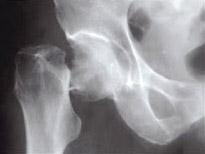

问题 男性,69岁,平素体健,在跑步时,不慎摔伤右髋部。X线如图,首选的治疗方法是 ( )

选项 A、全髋关节置换术 B、股骨头置换术 C、多根空心钉内固定 D、骨牵引 E、卧床,皮牵引

答案 A